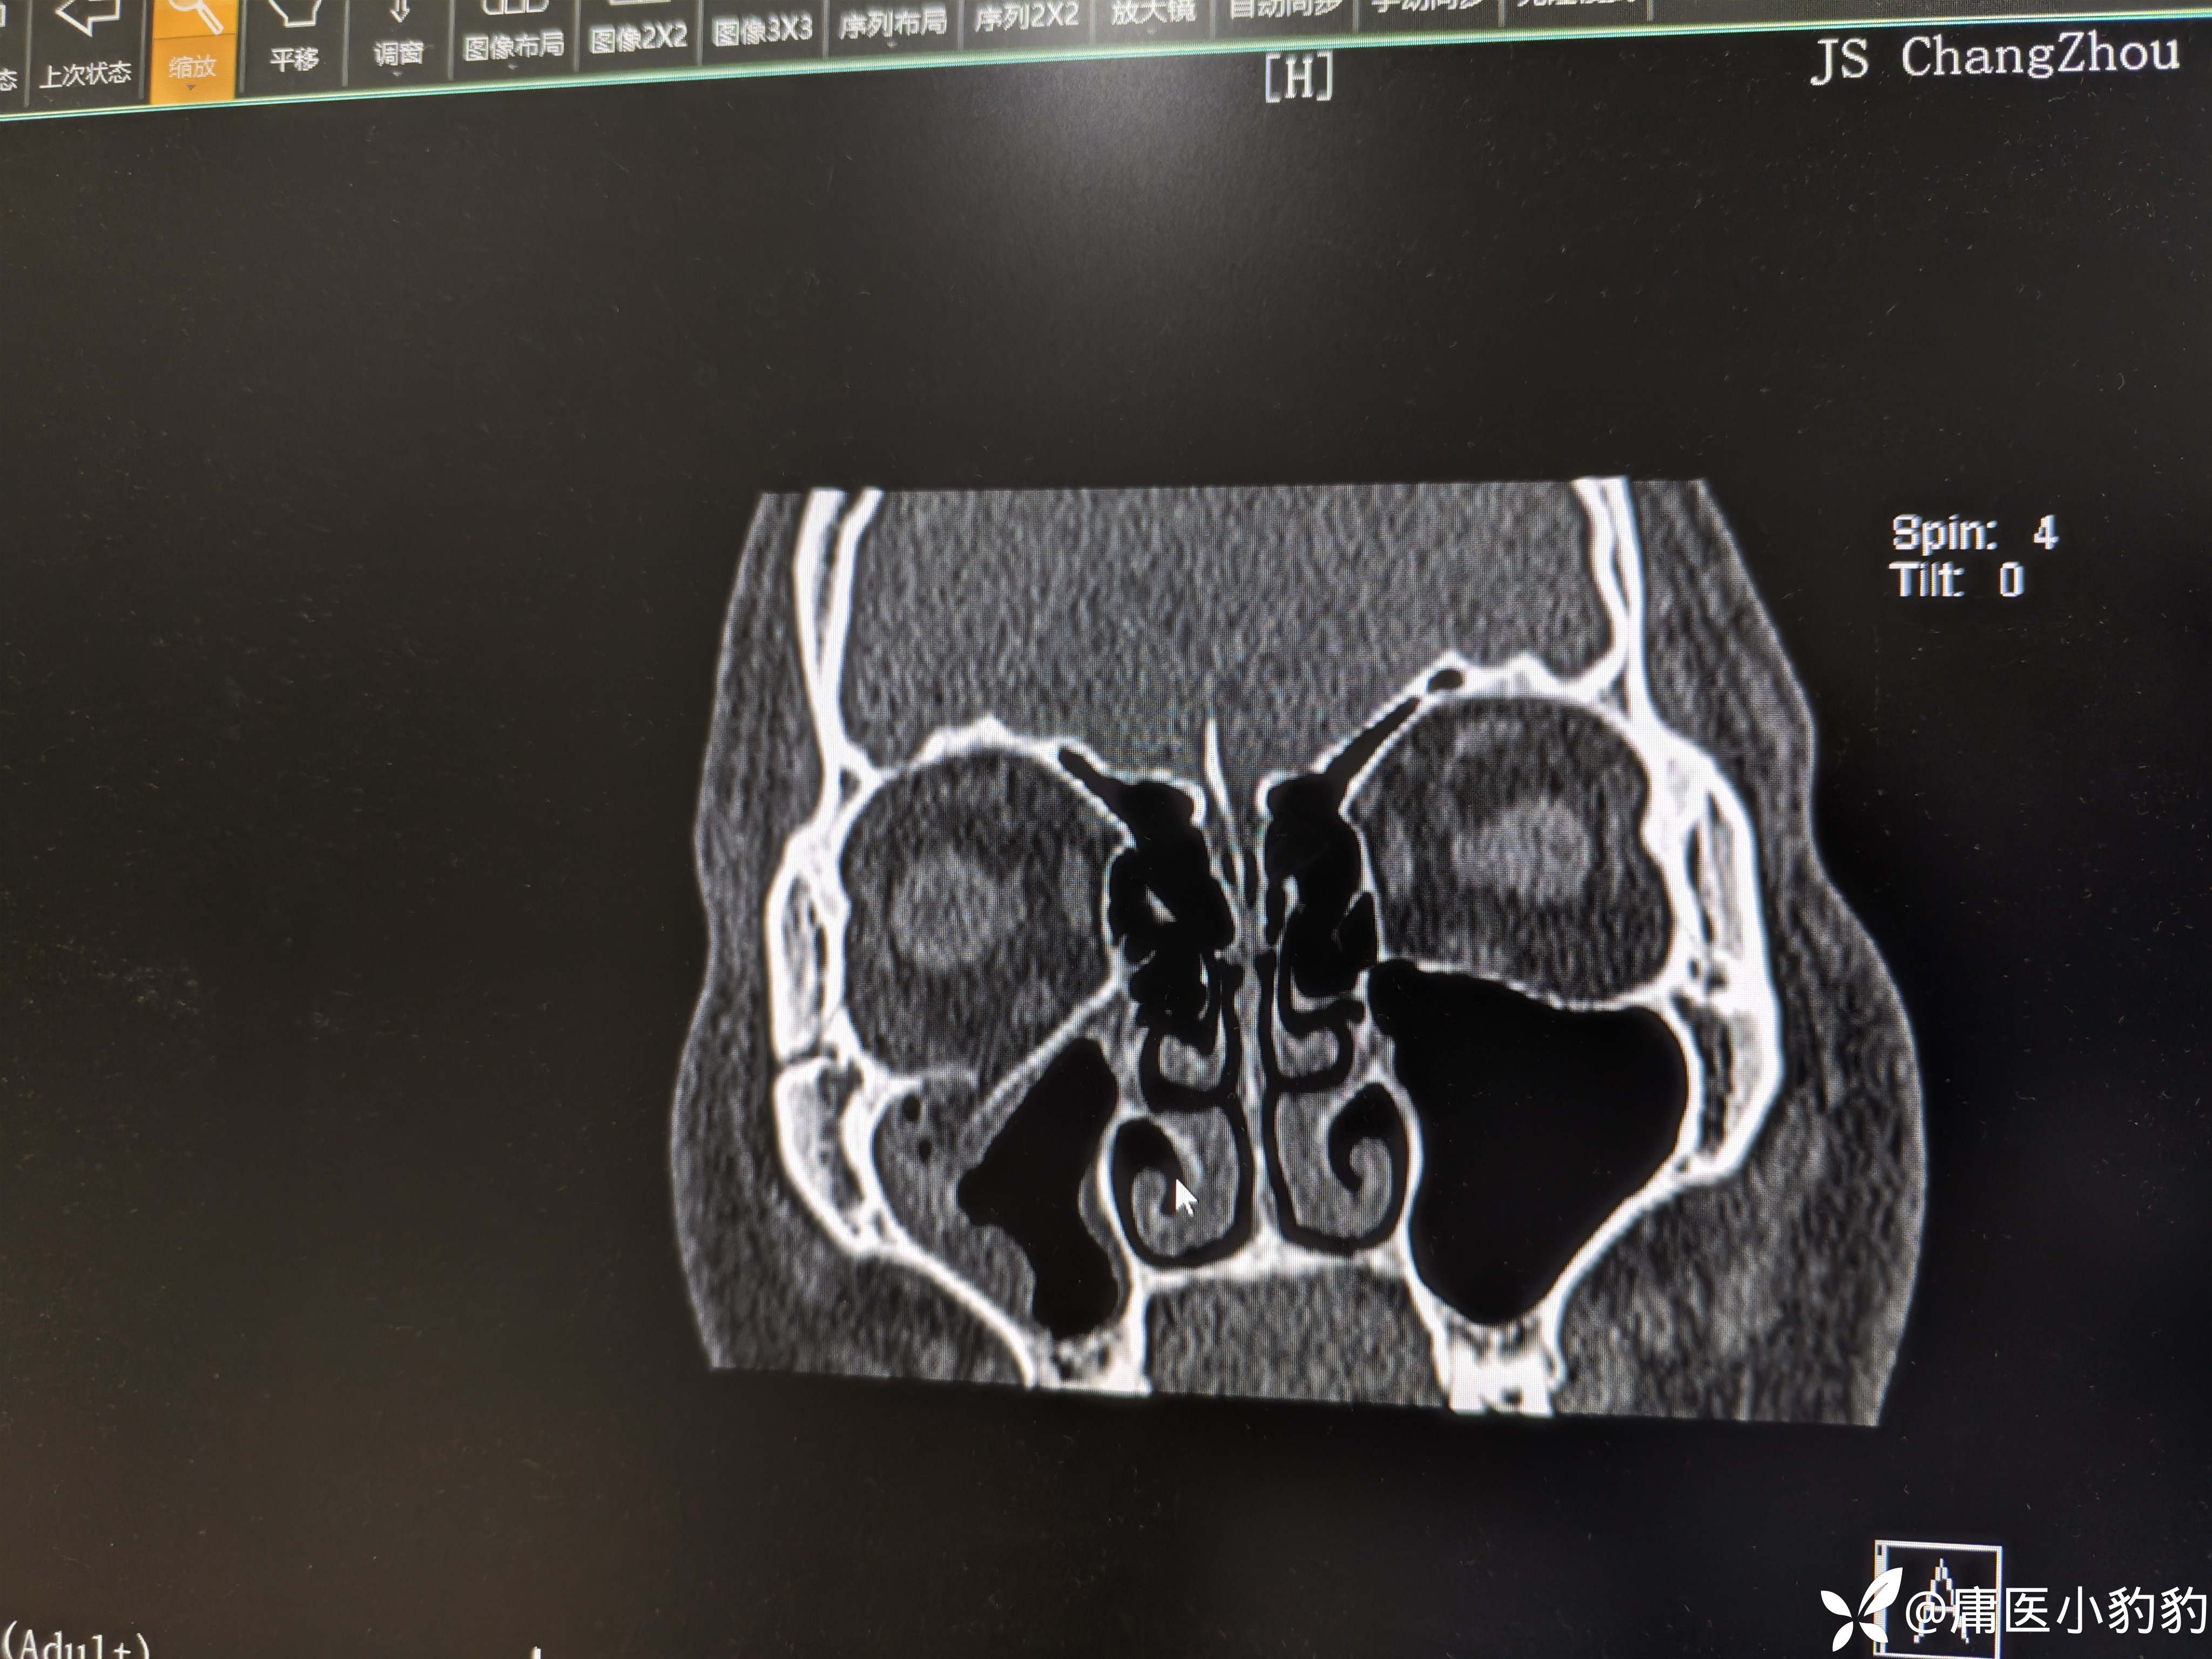

患者,男,26岁,五天前右面部外伤,右眼结膜下出血,主诉右眼视物模糊。眼眶CT示右上颌窦上壁骨折,右上颌窦内积血。眼科学检查示 矫正视力:右8.0/左1.0,眼压右18/左20,右眼视网膜震荡。无明显复视,重影,眼球运动未见明显受限,未行眼球牵拉试验。目前正在甘露醇+激素治疗观察。请问各位眼科的同门对该患者后续的治疗方案有何建议?